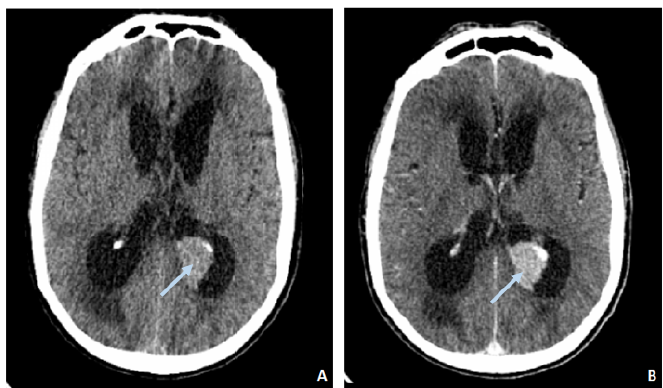

Choroid Plexus Metastasis of Papillary Thyroid Carcinoma Complicated by Intraventricular Hemorrhage

Zineb Izi, Hatim Essaber, Najwa Amsiguine, Soukaina Allioui, Asaad El Bakkari, Hounayda Jerguigue, Youssef Omor and Rachida Latib. 15(6): 20-22.